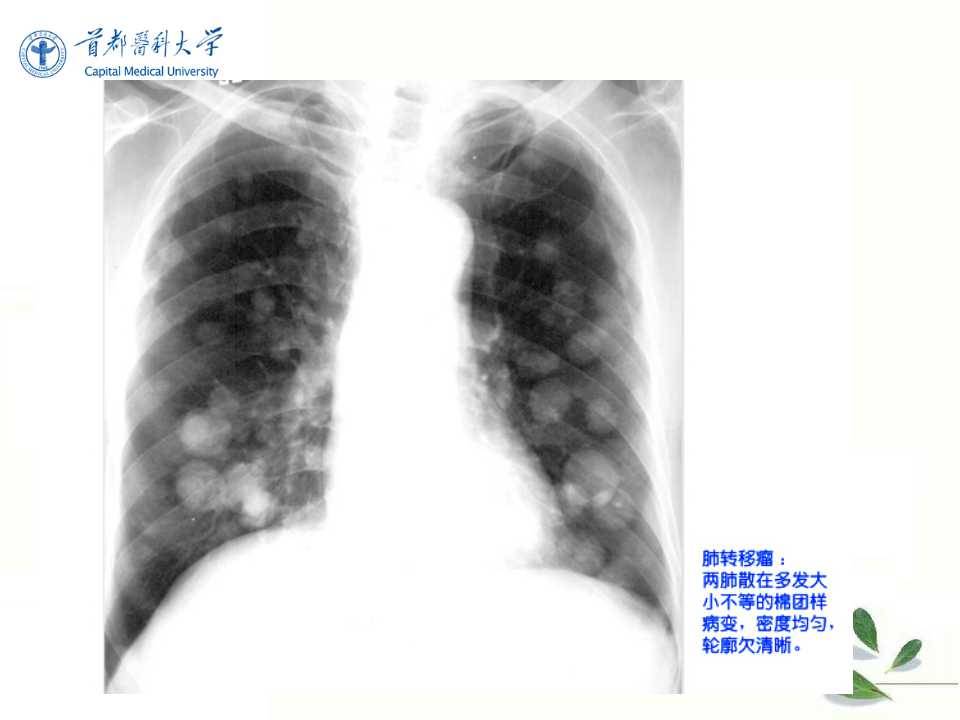

肺癌的影像学检查